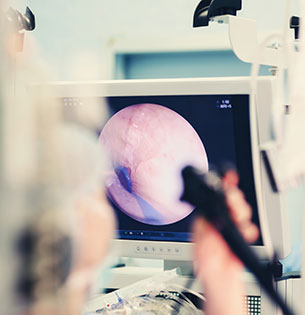

院長の専門は、消化器内科と内視鏡です。

胃カメラ、大腸内視鏡検査で、食道・胃・大腸などの病気の早期発見や治療を行います。

消化器や内視鏡の専門医として、2万件以上の内視鏡検査や治療を行ってきた経験を活かし、どんなささいなことでも相談でき、必要なときに必要な検査・治療を受けられるクリニックを目指します。